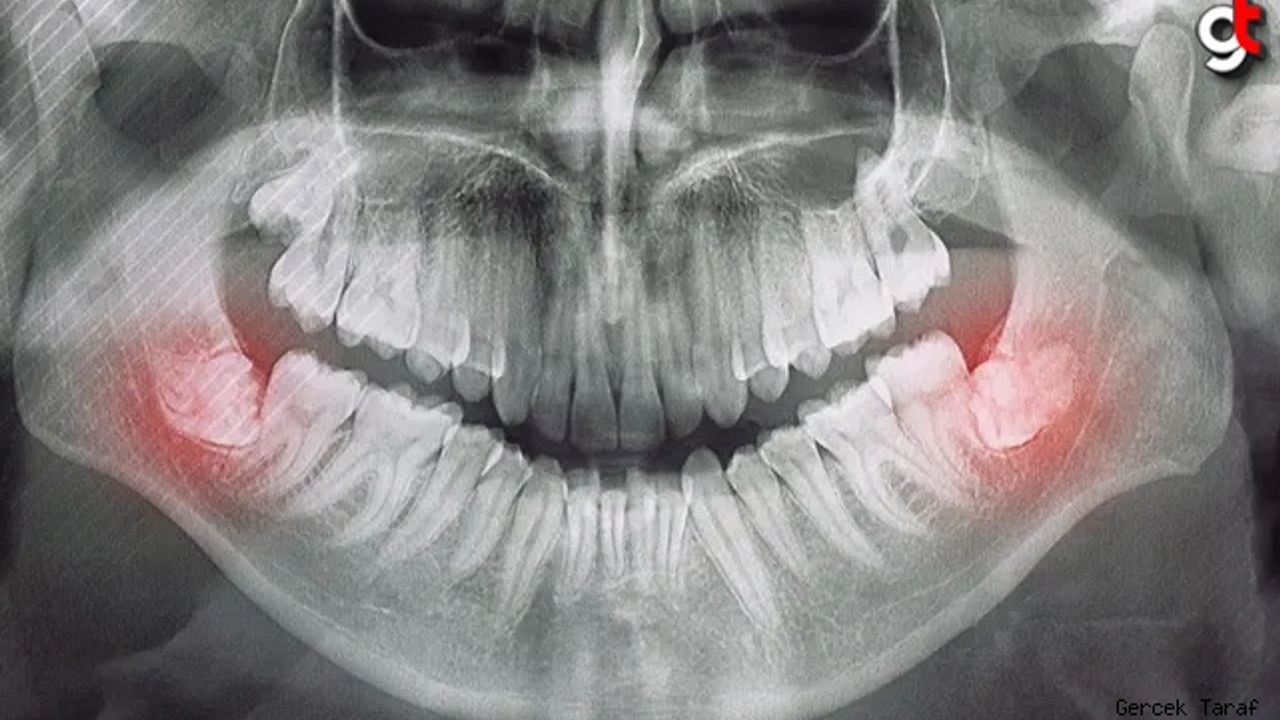

Sıkışma: Yirmilik dişlerle ilgili en yaygın sorunlardan biri, çenede tam olarak çıkmaları için yeterli alan olmadığında ortaya çıkan gömüklüktür. Gömülü yirmi yaş dişleri, çevredeki dişler veya kemik tarafından kısmen veya tamamen engellenebilir. Bu durum ağrı, şişlik ve enfeksiyon gibi çeşitli sorunlara yol açabilir.

Enfeksiyon ve Diş Eti Hastalığı: Kısmen sürmüş yirmi yaş dişleri, yiyecek parçacıklarının ve bakterilerin sıkışabileceği boşluk cepleri oluşturabilir. Bu durum diş eti hastalığının (periodontal hastalık) veya diş enfeksiyonlarının (perikoronit) gelişmesine yol açabilir. Yirmilik dişler sorun yarattığında ağrı yaygın bir semptomdur. Bu ağrı hafif bir rahatsızlıktan şiddetli zonklayıcı ağrıya kadar değişebilir ve kulağa, çeneye veya yüzün diğer kısımlarına yayılabilir.

Kistler ve Tümörler: Nadir durumlarda, kist veya tümör gelişimi gömülü yirmi yaş dişleri ile ilişkili olabilir. Bu büyümeler yakındaki dişlere, kemiklere ve sinirlere zarar verebilir.